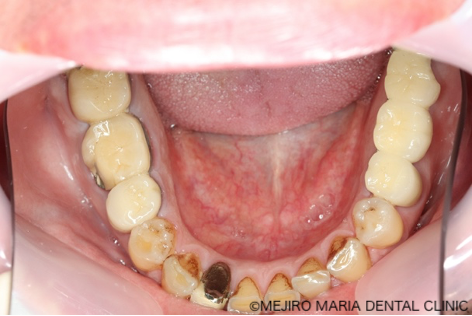

患者様は、長年にわたり臼歯部(奥歯)の噛み合わせの調子が悪いことと、食事の際に痛みを感じることを主訴に来院されました。前歯部から口腔内を確認すると大きなトラブルは確認できませんが、レントゲン撮影と口腔内診査を行うと、多数の臼歯部の歯牙(歯)が歯根破折により抜歯を余儀なくされる状況でした。

まずは、歯周組織検査を含めた口腔内診査、レントゲン写真の撮影により、保存できる歯牙と、抜歯をせざるを得ない歯牙などを選定しました。

今回の症例では、歯根破折していた5本の歯牙(下の写真・赤矢印)に対して、抜歯を提案した。また、診断用WaxUp(ワックスアップ)を行ったところ左下のブリッジ(青丸)と右下(青矢印)の噛み合わせ平面が乱れており、咬合に負担をかけていることが予想されました。そのため、最終的にそれらの不調和を改善し、適切な噛み合わせにすることをゴールとして治療を開始しました。